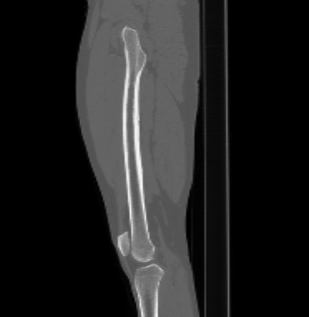

Бедренная кость является наиболее крупной трубчатой костью скелета человека и выполняет основную опорную функцию, обеспечивая прямохождение человека. Головка бедренной кости соединяется с вертлужной впадиной костей таза, образуя тазобедренный сустав, обеспечивающий движения нижней конечности.

КТ предусматривает использование рентгеновского излучения, которое хорошо поглощается костной тканью. В результате сканирования и последующей цифровой обработки полученных данных получаются подробные снимки в различных плоскостях, а также трехмерные изображения бедренной кости и тазобедренных суставов, которые можно увеличить и повернуть в разные стороны.

Снимки высокого разрешения позволяют выявить минимальные изменения в костных структурах и окружающих тканях. Мультиспиральная КТ может применяться в экстренных ситуациях для диагностики травматических повреждений бедренной кости и тазобедренных суставов, в частности, при переломах шейки бедра. Кроме того, исследование незаменимо при планировании оперативного вмешательства, а также в послеоперационном периоде для оценки успешности проведенной операции и для отслеживания процесса восстановления.

КТ бедренной кости помогает выявить воспалительные изменения, очаги деструкции костной ткани, доброкачественные и злокачественные новообразования. При подозрении на опухолевый процесс дополнительно применяется контрастное усиление. Для этого пациенту внутривенно вводится контрастный препарат на основе йода, который в большей степени, чем окружающие ткани, поглощает рентгеновские лучи. Поэтому при попадании в опухолевые очаги он обеспечивает их яркую визуализацию на снимках КТ. Методика контрастирования помогает обнаружить опухоли минимальных размеров, определить точные границы опухолевого очага, степень его прорастания в окружающие ткани, эта информация необходима врачу для назначения эффективной тактики лечения.